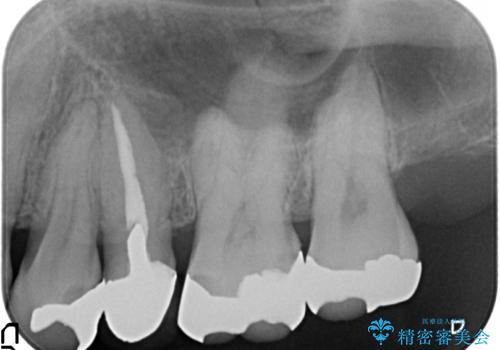

- 左上の奥歯を綺麗にしたいといらっしゃった方の症例です。

左上4、5、6、7番目の歯をオールセラミッククラウンにより補綴しました。

- オールセラミッククラウン…¥100,000、仮歯…¥10,000、ファイバーコア…¥20,000、精密根管治療費別途費用は治療当時の料金となります